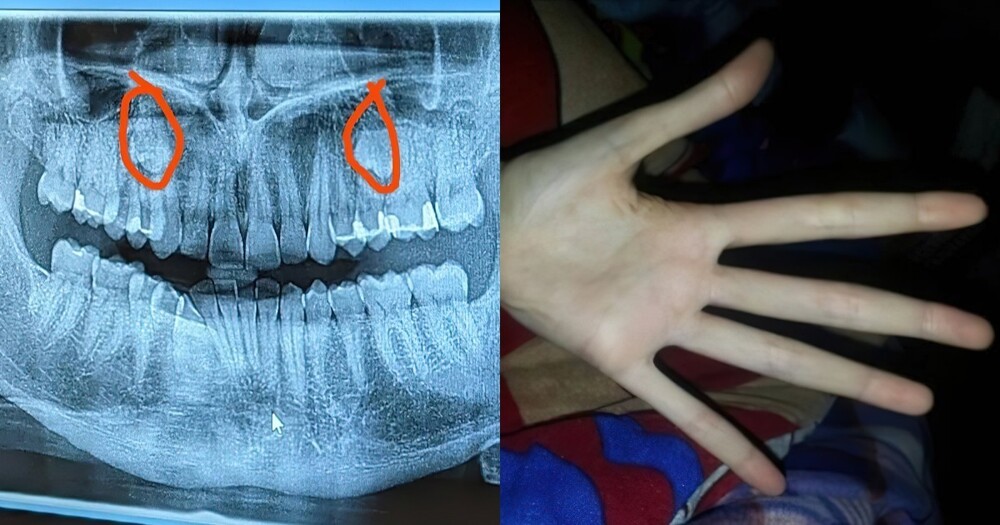

15. A man went to the dentist complaining of pain and found out that he had extra teeth.

- Supernumerary teeth. Should have been cured when you were younger, you would have more opportunities. It can be transmitted by inheritance.